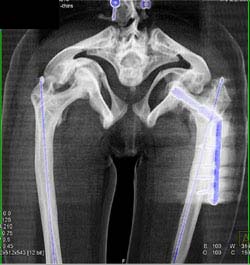

Diagnosis

Fracture/dislocation